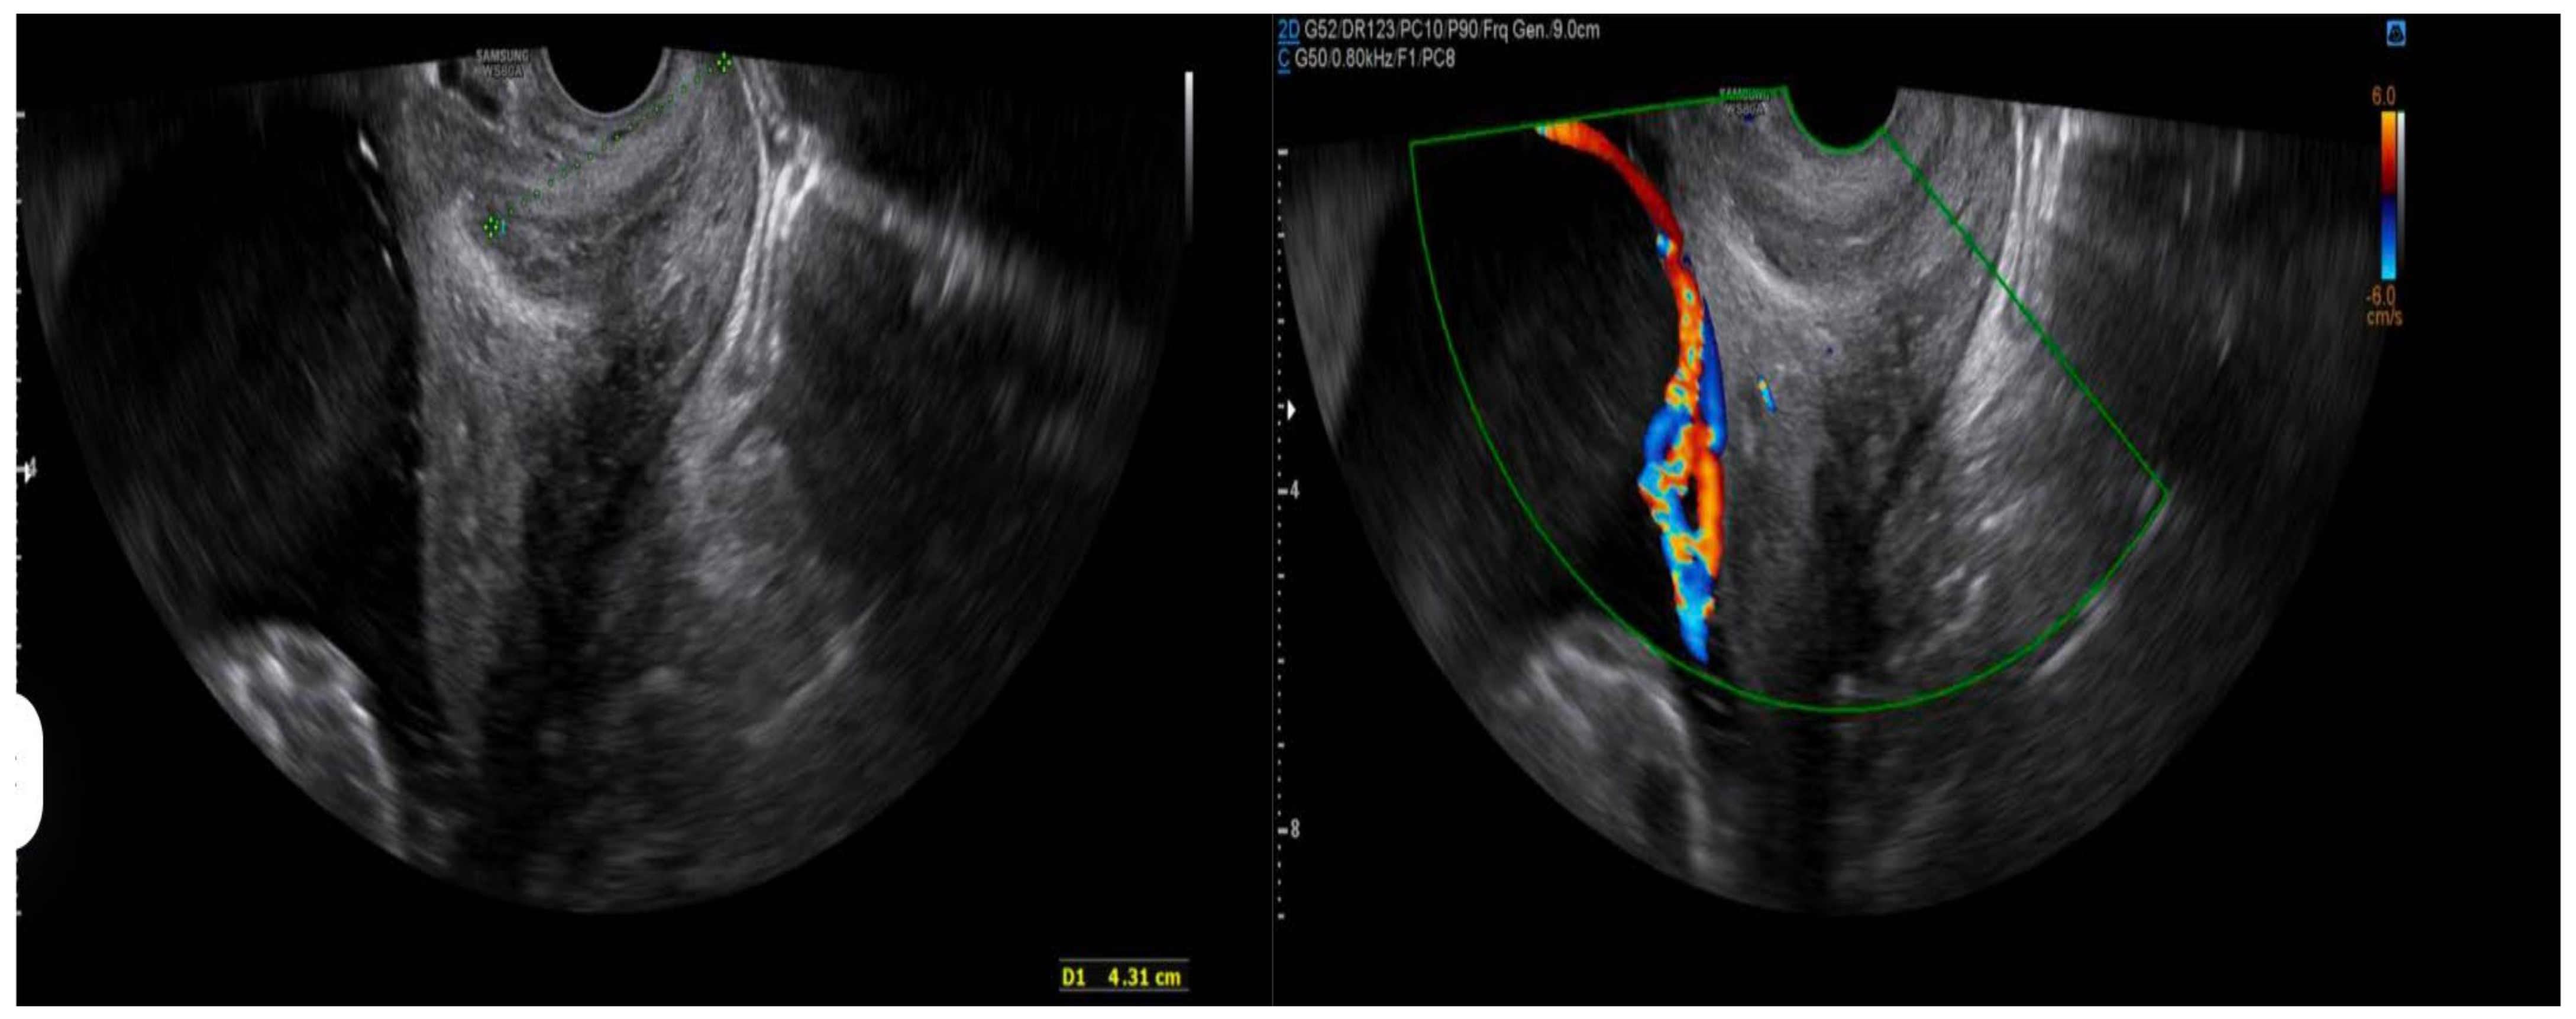

- Prenatal ultrasound evaluation: morphological description of the main placenta and accessory lobe, precise determination of umbilical cord insertion site, color Doppler assessment of vascular connections between lobes, and transvaginal ultrasound to rule out vasa previa.

- Transvaginal ultrasound to rule out vasa previa in selected cases.

- Selective transvaginal ultrasound

- Indicated when accessory lobes are low-lying or Doppler imaging reveals vessels near the internal cervical os.